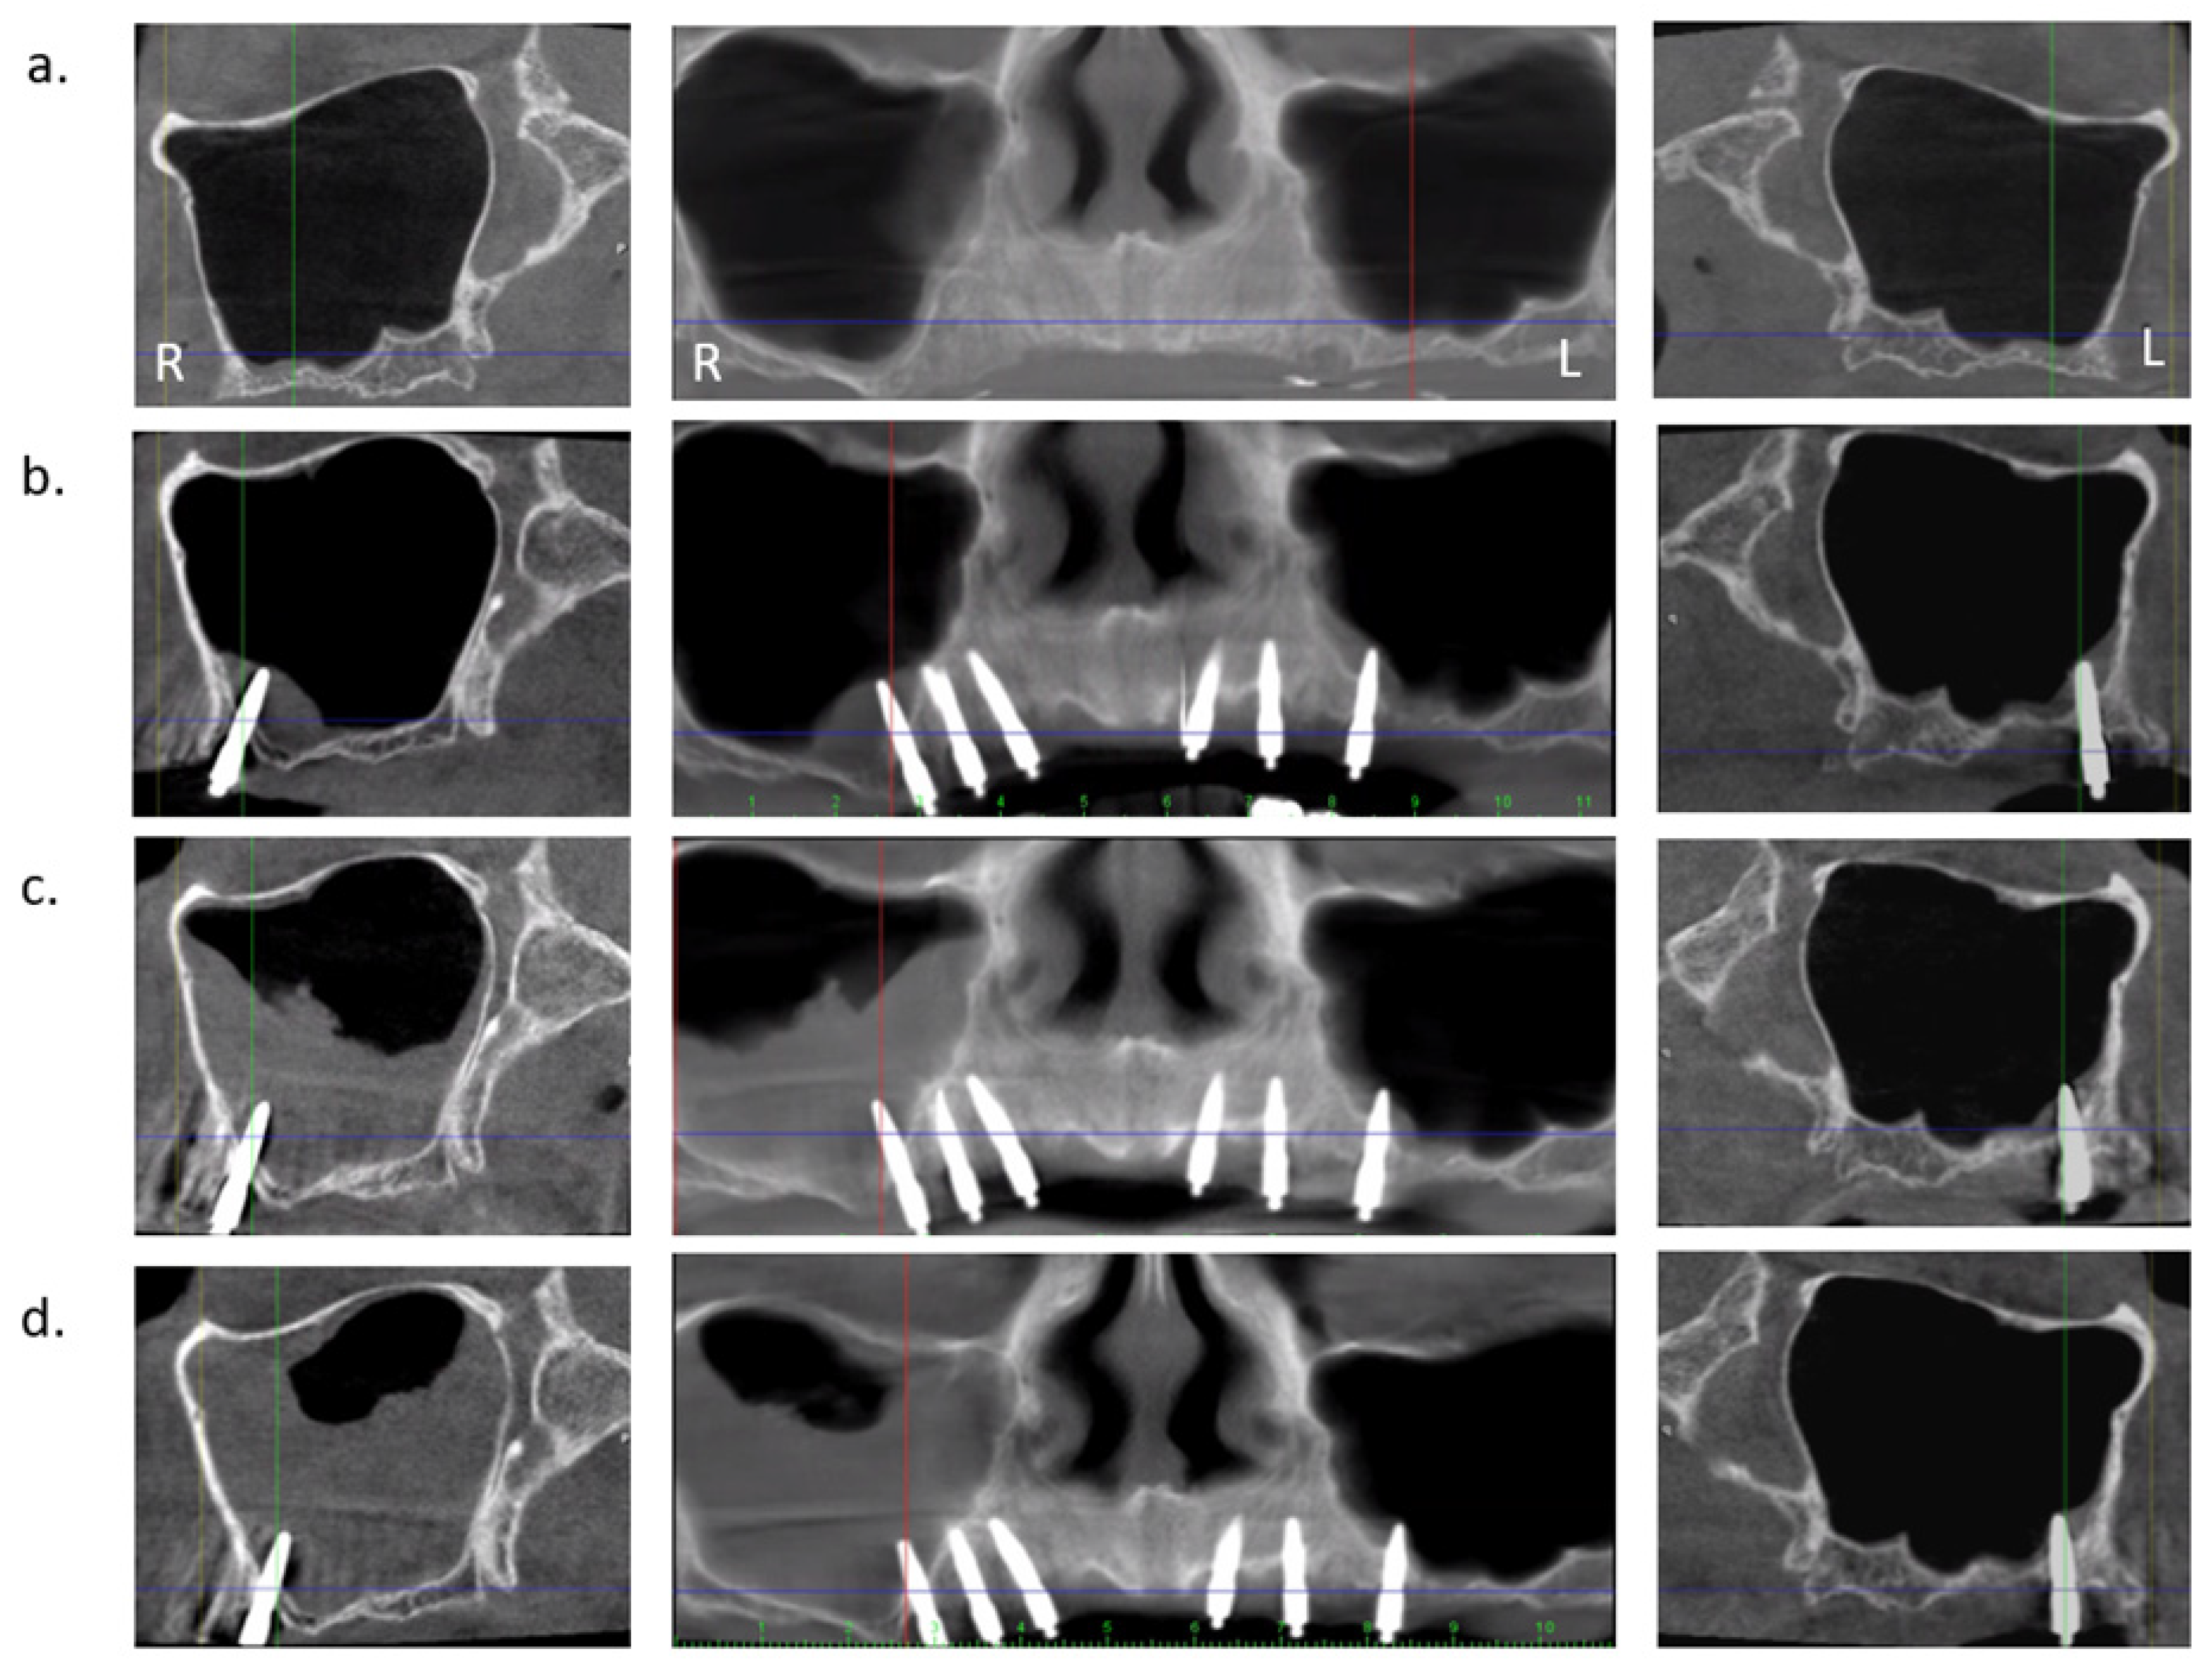

2.2. Radiological Examination